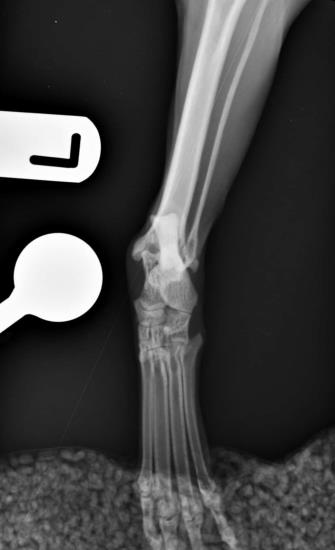

The radiographs below show a caudocranial “stressed” view of the left tarsus.

A gap between the distal tibia and the talus can be noted and this is a result of medial collateral ligament failure which had led to instability of the tarsus. This injury is often traumatic in nature and several treatment options are available, including permanent joint fusion (pantarsal arthrodesis).